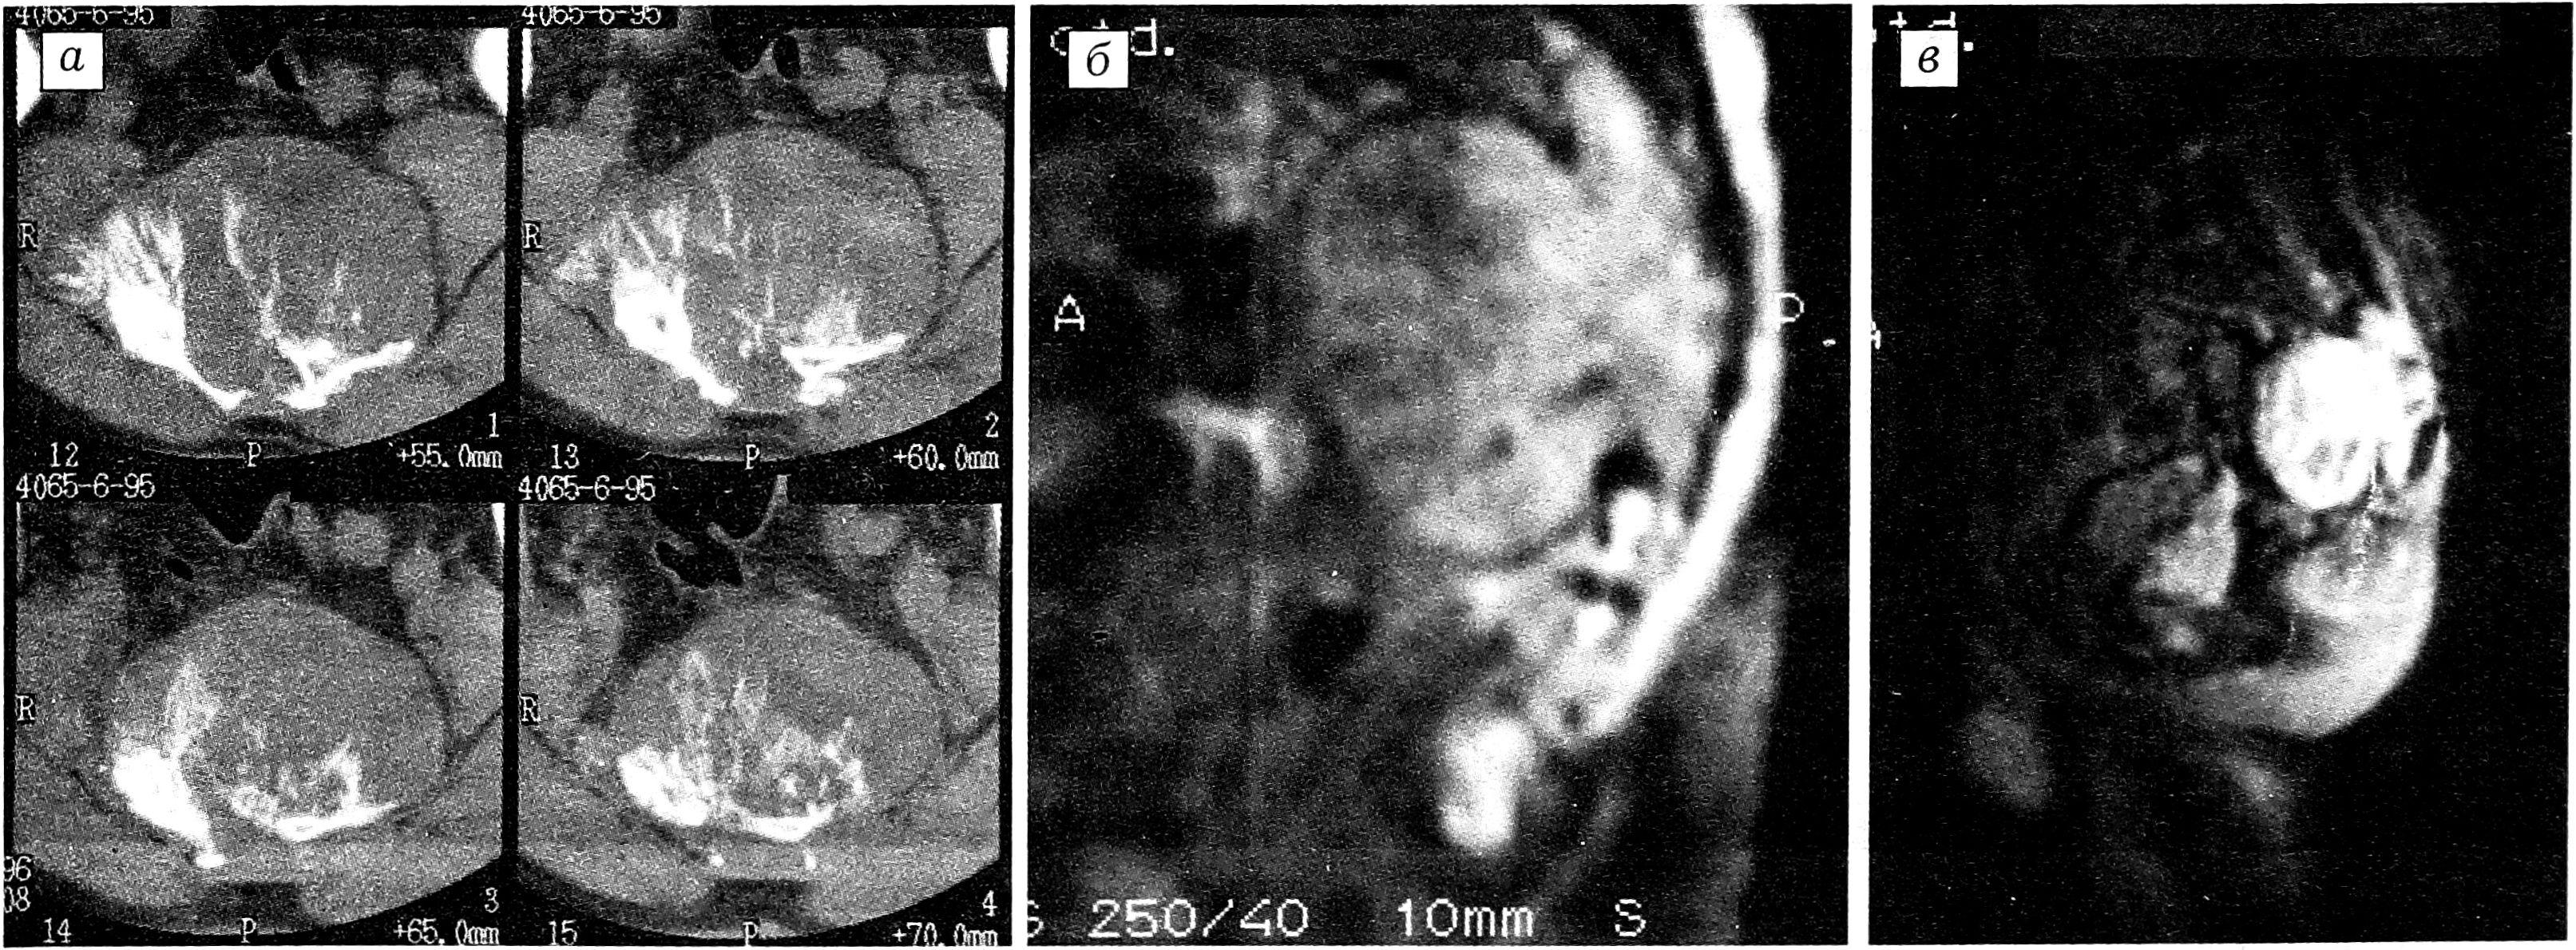

Рис. 1. Больной О., 19 лет. Диагноз: остеогенная саркома крестца, рецидив. КТ.

Состояние после резекции правого крестцово-подвздошного сочленения с замещением дефекта трубчатым аллотрансплантатом. Рецидив остеогенной саркомы S1. Отчетливо прослеживается структура рецидивного узла. Справа — объемная реконструкция изображения.

Рис. 4. Больной М., 34 лет. Диагноз: неврилеммома S3-S5, рецидив, озлокачествление.

a — аксиальная КТ: остеолитический очаг деструкции S3-S5, экстравертебральный компонент опухоли, грубые обызвествления и костеобразование; б — Т1 взвешенные МРТ в сагиттальной проекции: изоинтенсивный гетерогенный сигнал от опухоли в форме «песочных часов», гипоинтенсивный сигнал от капсулы; в — Т2 взвешенные МРТ в сагиттальной проекции: гиперинтенсивный сигнал от опухоли.